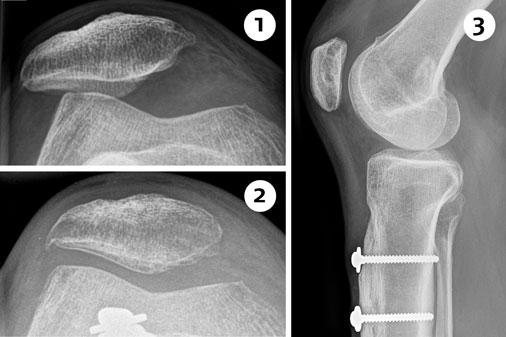

Bei diesem Eingriff wird der knöcherne Ansatz der Kniescheibensehne (Patellarsehne) am oberen Schienbein gezielt versetzt. Das Ziel ist, die Position und die Laufbahn der Kniescheibe zu verbessern und dadurch Schmerzen, Instabilitäten oder Luxationen (Ausrenkungen) zu verhindern.

Ist die gewünschte Position erreicht wird der abgelöste Knochenblock wieder mit Schrauben am Schienbein fixiert. Oft wird dieser knöcherne Eingriff mit einer weichteiligen Korrektur kombiniert – zum Beispiel einer MPFL-Plastik –, um ein möglichst stabiles und schmerzfreies Ergebnis zu erzielen.

Im Röntgenbild vor der OP ist die seitlich versetzte Patella erkennbar (1). Nach einer operativen Korrektur der Patellarsehne hat sich die Position der Kniescheibe deutlich verbessert (2). Die seitliche Aufnahme zeigt die Verschraubung des Knochenblocks mit der daran ansetzenden Sehne am Schienbein (3).